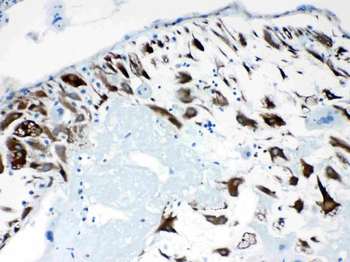

10 μg, 100 μg - Anti-S100 alpha 6/S100A6 Antibody [orb315184]

FC, ICC, IF, IHC, WB

Human, Mouse, Rat

Rabbit

Polyclonal

Unconjugated

10 μg, 100 μg - Anti-HSD11B2 Antibody [orb316541]